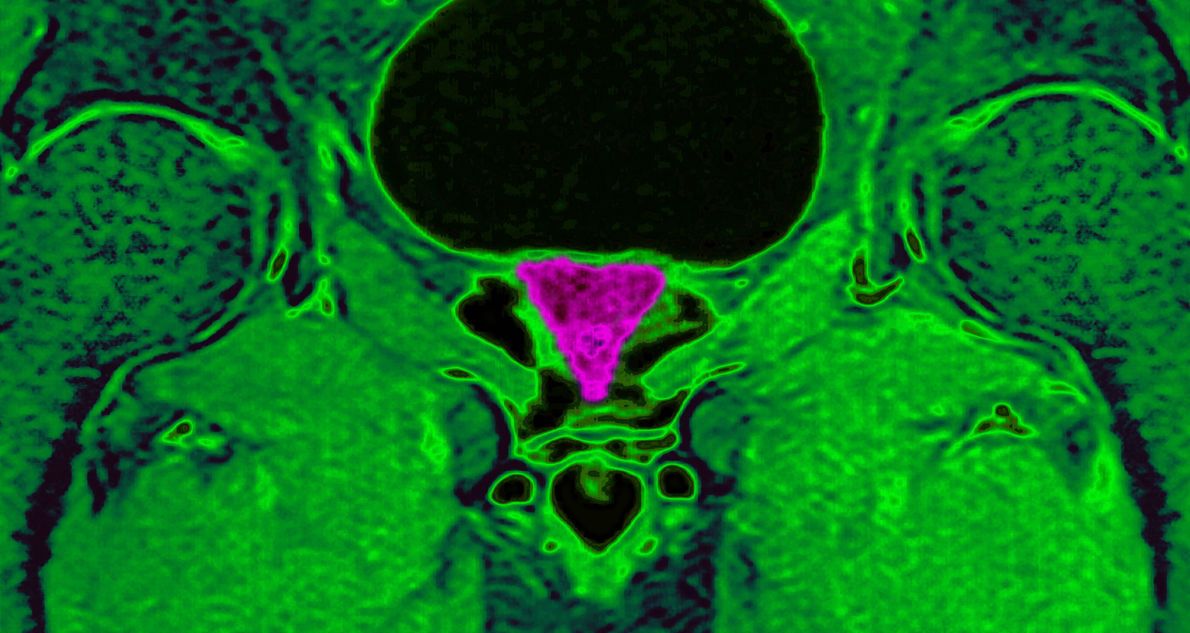

Η δακτυλική εξέταση και η κολονοσκόπηση θα δείξει φλεγμονή ή καρκίνο. Επίσης, η ουροδυναμική μελέτη είναι χρήσιμη για την εκτίμηση των συμπτωμάτων του ουροποιητικού που σχετίζονται με παθήσεις του προστάτη. Επίσης, το PSA-Prostatic Specific Antigen μετρά τη φλεγμονή του προστάτη.